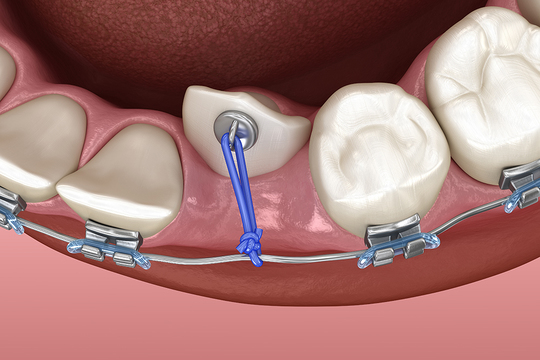

歯科矯正用アンカースクリュー

ワイヤー矯正では通常、奥歯などの動きにくい歯を支点にして歯を動かします。対して歯科矯正用アンカースクリューを使った矯正では、直径1.3~2.0㎜のチタン製の小さなネジをあごの骨に埋め込み、そこを支点にして歯を移動させます。

これにより、従来の矯正治療では動かしにくかった方向にも歯を移動できるようになりました。前述した「矯正治療が難しい4つのケース」においても、歯科矯正用アンカースクリューの使用によって治療が可能になることは少なくありません。

埋まっている歯を矯正するケース

埋伏の度合いが重度な歯は、一昔前ならば抜歯の対象でした。

しかし当院には、歯科用CTの画像で歯ぐきの中の状態を確認し、埋伏歯の上のあごの骨を除去しながら歯を露出させる技術があります。そして露出させた歯に器具をつけ、適正な方向に引っ張り出す「外科的開窓牽引(げかてきかいそうけんいん)」という処置が可能です。

この処置と矯正治療を併用すれば、重度の埋伏歯であっても歯ぐきから引っ張り出し、きちんと歯を並べて整えられる確率が高まります。